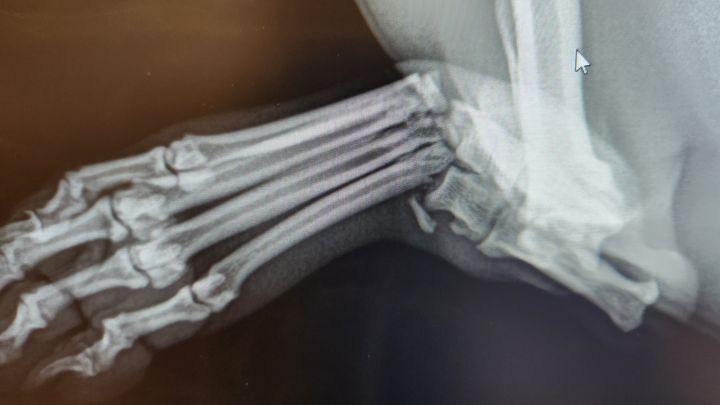

Our sweet Jack Russell mix had a mishap with our Corgi and sustained not just a broken tarsal, but a dislocation as well, the initial visit with blood work and orthopedic consult is $1449.93 then the estimated surgery cost is about $2500-$4000 not including blood work, follow ups and pain meds. This is a tough time of year for Sam and Rosey needs pins surgically inserted to fuse the bones. Rosie will lose most of her mobility and range of motion without the surgery. The funds are currently not available to help this sweet girl. Our only other option is forego surgery and attempt to let it heal with a huge risk of it not healing correctly and her being crippled for the rest of her life. We are hoping even a few people can help out since every penny counts right now.

UPDATE: The money had that has been raised has gone to Rosey's orthopedic follow-up and her reevaluation getting a hard cast. The goal has been adjusted to cover the Orthopedist, cast, PT and last follow up with xrays!